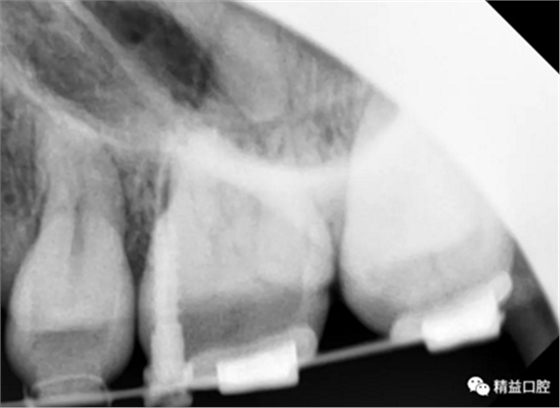

初次看到俊的牙片,我也驚訝到了,畢竟才27歲,上下門牙牙根吸收得非常嚴重,如果矯正,其中的風險還是非常大的。

從片子上可以清除看到,上牙門牙牙根吸收非常厲害。